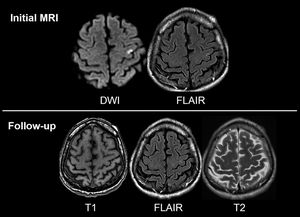

MRI differences

Brain

Mri

Imaging

Dwi